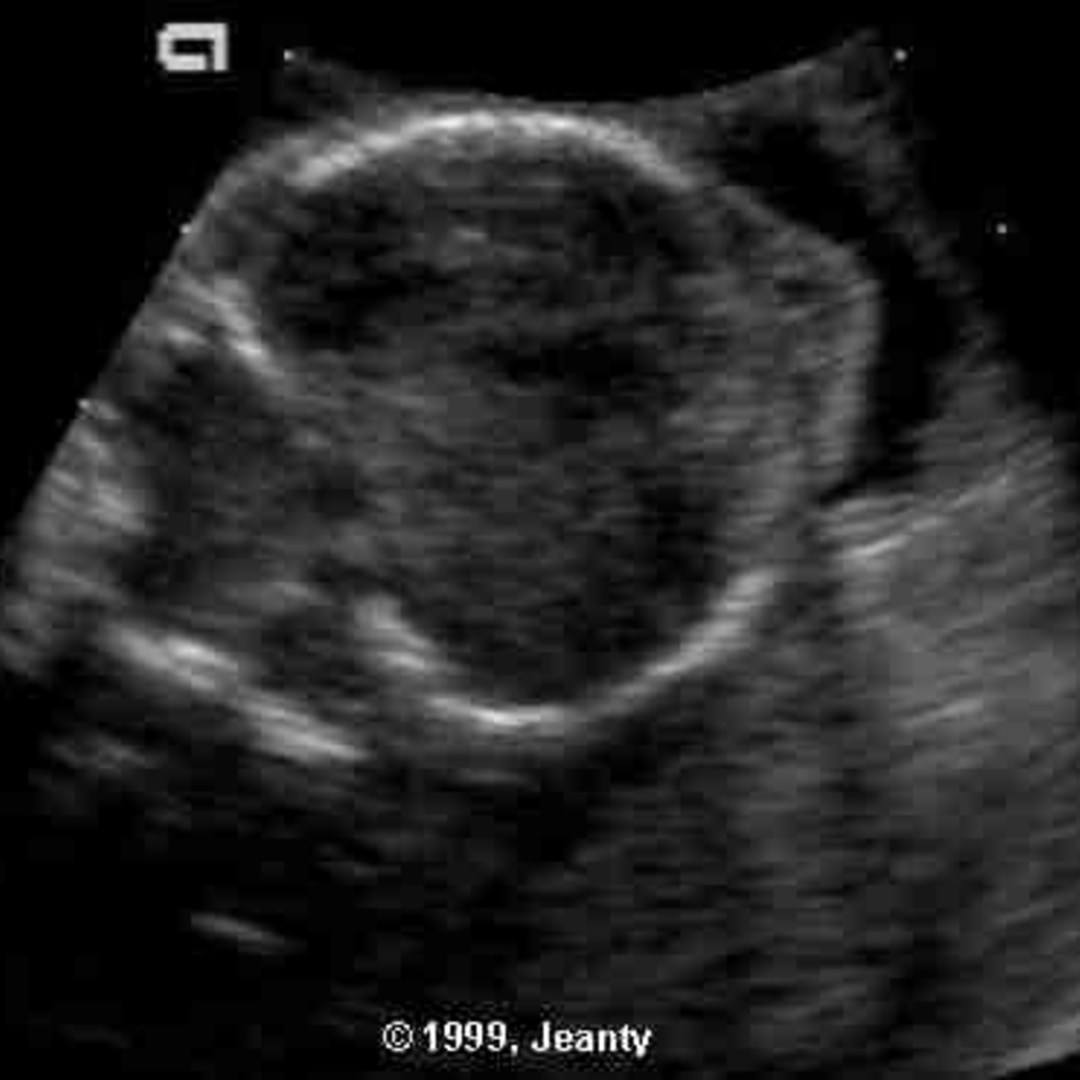

Warburg Disease.  — warburg micro syndrome (warbm) is a rare autosomal recessive genetic disorder.

— warburg micro syndrome (warbm) is a rare autosomal recessive genetic disorder.